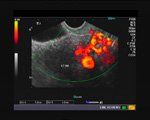

What is your diagnosis of this ultrasound image?

Test your ob/gyn ultrasound knowledge in our DailyDx.

Test your diagnostic skills!